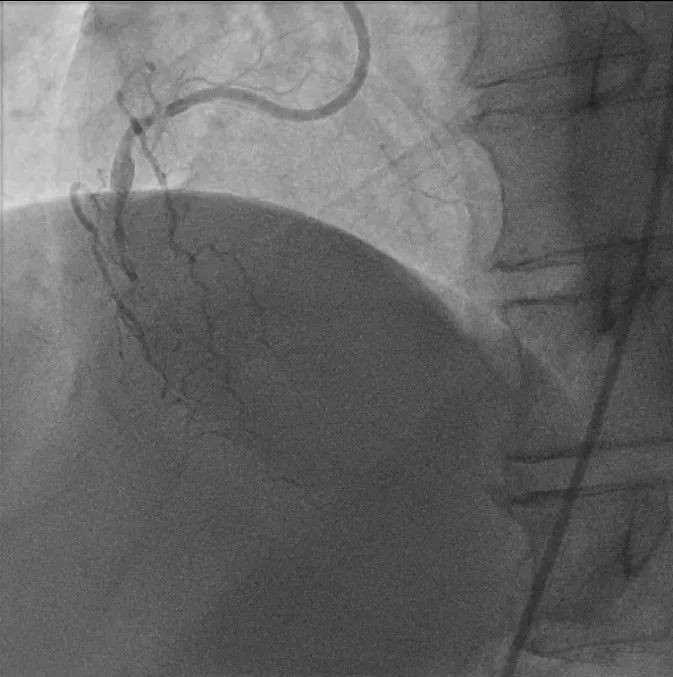

▲右冠脉闭塞情况(治疗前)